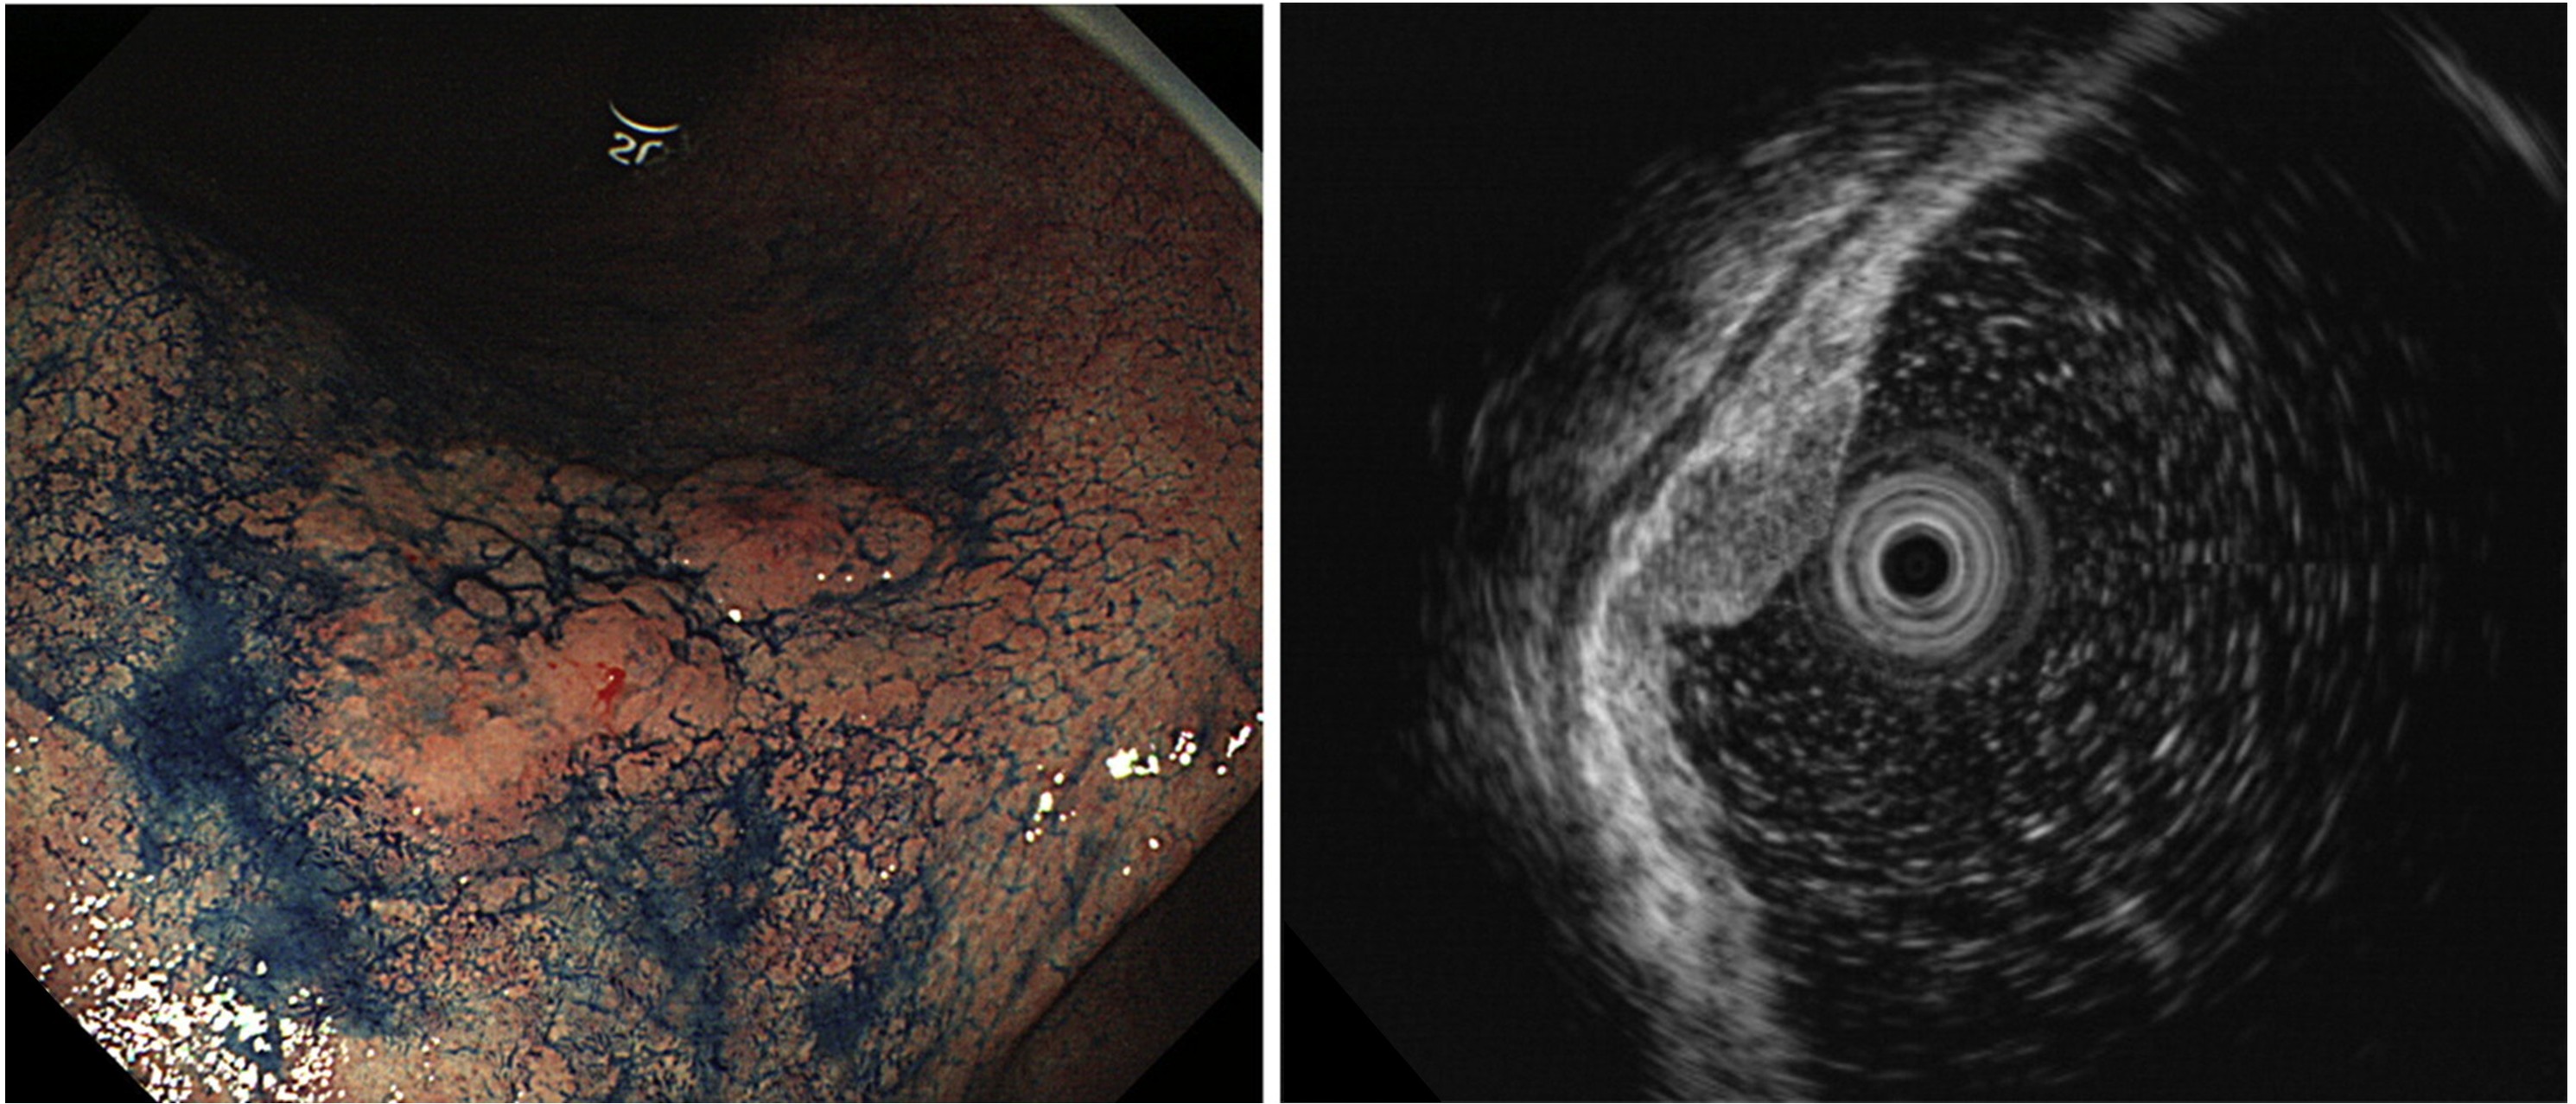

画像強調内視鏡(IEE)や拡大観察、超音波内視鏡を駆使して、病変の正確な診断と早期発見に努めています。治療においては、ESDによる低侵襲治療に加え、切除不能・再発胃癌に対しては遺伝子関連検査(バイオマーカー検査)に基づいて治療を選択し、化学療法や分子標的薬、免疫チェックポイント阻害薬を用いた薬物療法を行っています。

食道・胃・十二指腸・大腸に発生する早期消化管癌に対し、内視鏡的粘膜下層剥離術(Endoscopic Submucosal Dissection:ESD)を中心とした低侵襲治療を積極的に行っています。治療に先立っては、最新世代の内視鏡機種および高性能光源を用いた精緻な観察を行い、拡大観察や画像強調内視鏡、超音波内視鏡を用いてによって病変の質的診断・深達度診断を高精度に評価します。そのうえで、外科を含む多職種と十分に協議し、患者さん一人ひとりの病状に応じて治療方針を検討しています。

図2. 超音波内視鏡を用いた胃癌の深達度診断